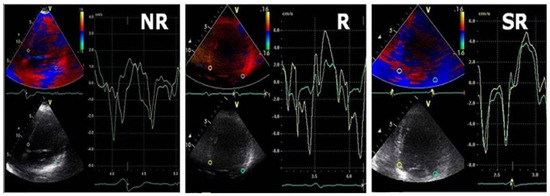

Among the baseline echocardiographic parameters in responders when compared with non-responders, DD profile improved in 65% of patients, reaching a significant statistical importance in E/E′ ratio both in super-responders and in responders. Both E″T and A″T were significantly decreased in responders when compared with baseline (76 ± 13 vs. 51 ± 11 and 26 ± 8 vs. 7 ± 5), and the non-responders group was associated with larger baseline E″T and A″T and no statistically significant difference was noted in these patients after CRT. (Figure 2 and Figure 3).

Figure 2.

Typical TDI patterns in LV fusion pacing in SR/R/NR groups; green line = lateral velocity curve, yellow line = septal velocity curve.